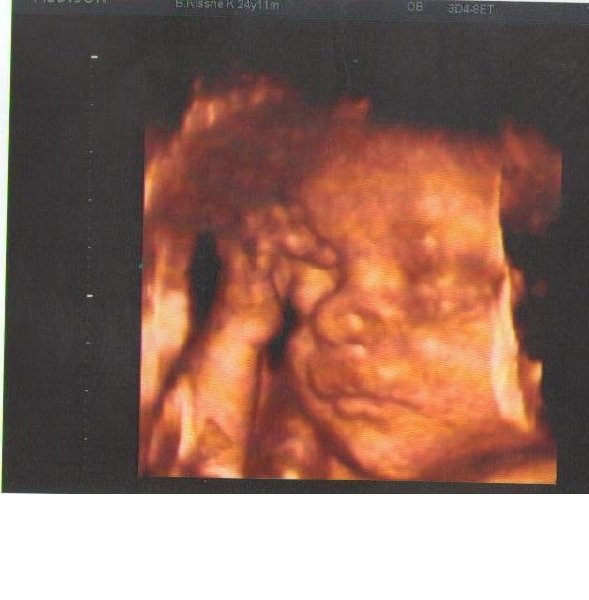

Baba fekvése: Nálam többnyire fejvégűek, de Mira komoly forgolódást rendez, az utóbbi két UH-n teljes fordulatot sikerült végignézni. Szóval még bármi lehet. Akik már a 29-30. hét környékén járnak szintén tapasztaltak olyat, hogy egy kicsit csökkent, lassult a magzatmozgás? A "szakirodalom" szerint ilyenkor a korábbi focimeccseket már felváltják a finomabb mozgások, lábak, könyök, popsi kinyomogatása, de azért én egy kicsit mégis aggódom.